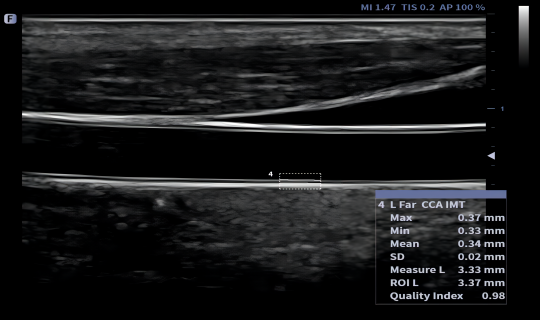

Automatyczna identyfikacja i pomiar grubości błony wewnętrznej i środkowej (intima-media). Możliwość pomiaru zarówno lewych, jak i prawych naczyń krwionośnych oraz ścian przednich i tylnych.